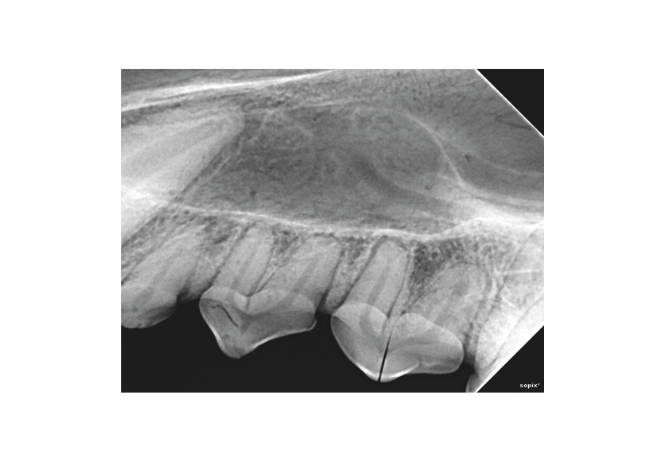

Sopix® Series visually differentiates dental tissues and provides a reliable image of the tooth anatomy, guaranteeing safe and rapid diagnosis.

FIBER2PIXEL® technology is based on the use of broad-spectrum optical microfibers to guarantee image clarity and contrast.